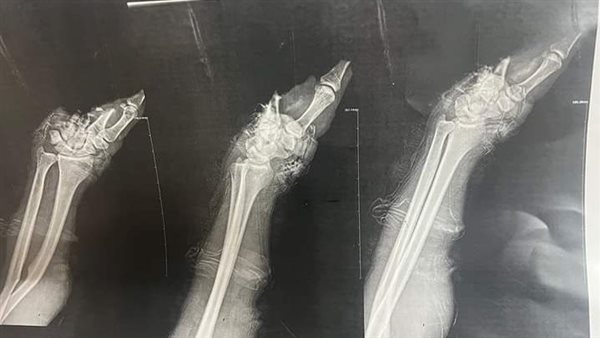

أعلن الدكتور أحمد القاصد، رئيس جامعة المنوفية، نجاح فريق طبي بقسم جراحة التجميل بالمستشفيات الجامعية في إعادة يد شاب مبتورة للحركة بعد عملية جراحية ناجحة استغرقت 10ساعات.

وعلى الفور تم اتخاذ الإجراءات الطبية اللازمة ونقل المريض إلى غرفة العمليات وإجراء جراحة ميكروسكوبية دقيقة للمريض تم فيها تثبيت العظام وتوصيل الشرايين والأوردة والأعصاب وإعادة كف اليد المبتور بنجاح، مضيفا أن المريض في حالة صحية جيدة=.